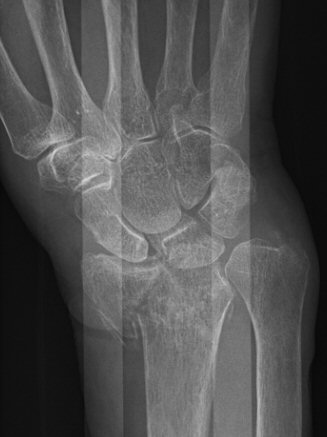

- Chauffeur: avlösning av proc. styloideus radii. Kan bero på luxation av handled, med associerade allvarliga ligamentskador.

Chauffeur-fraktur